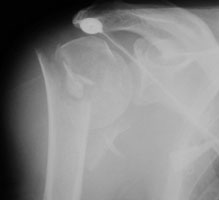

- Click on the image for a larger versionAAP radiograph of the left shoulder. This shows a minimally displaced fracture of the left humeral neck (Neer one-part).